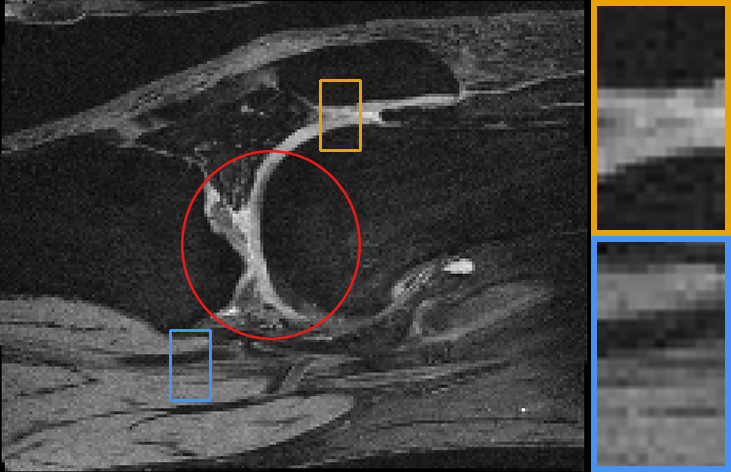

Our representative registration results are given in Fig. 7 and Fig. 8. The first three registration cases in Fig. 7 contain image-to-atlas on T1 brain MR, image-to-image on T1 brain MR and T2 brain MR test pairs. The large deformations in scans make registration challenging and difficult. As a result, all the source images are well aligned to the target. The second three rows in Fig. 8 contain knee T1 MR data, multi-modal data, and lung CT inspiration-expiration images. Although large deformations and intensity differences exist in scans, source images are well aligned to the target, demonstrating our outstanding performance.